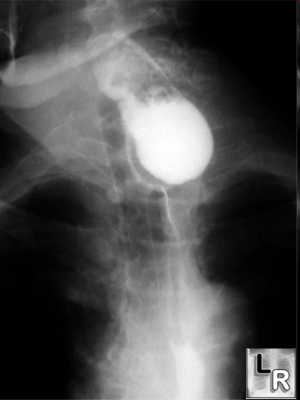

Diaqnozun dəiqiləşdirilməsi üçün kontrastlı Rentgenoloji müayinələr, KT və çox ehtiyatla endoskopiya edilir.

- Kontrastlı Rh-qrafiya - diaqnozu dəqiqləşdirən müayinədir.

- Rentgenoqrafik divertikul görünməsi

Kontrast məhlulunn divertikul nahiyəsində toplanması

|